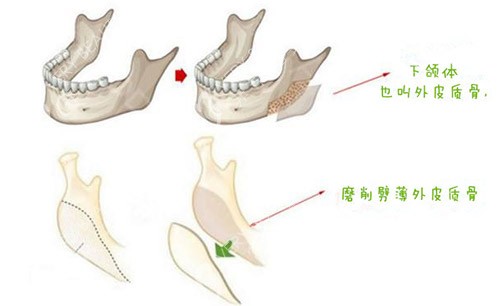

下颌角处理的独到之处

他倾向保留生理性角度的自然做法。并非一味追求极致V脸结果。使术后侧面轮廓线条流畅真实。做到“显小不显假”的自然感。

如何应对皮肤松弛风险

骨量减少可能引发软组织下垂。他在术中会采用组织悬吊固定。将肌肉和皮肤复位到适当位置。必要时结合辅助方式维持紧致。